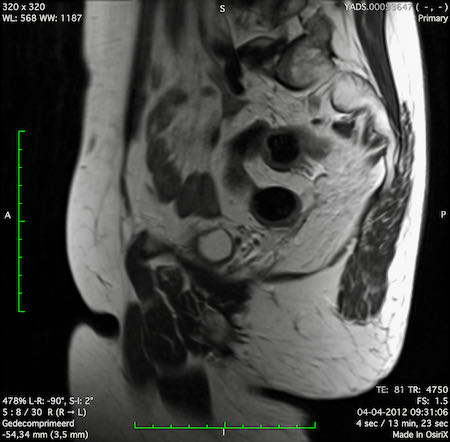

Hình ảnh

Các hình ảnh được cung cấp cho thấy ung thư biểu mô tế bào nhẫn với tình trạng dày lan tỏa thành trực tràng, hình ảnh bia bắn điển hình, và sự xâm lấn mỡ mạc treo trực tràng.